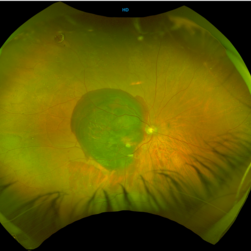

RPE rip in a case of Idiopathic polypoidal choroidopathy RPE rip in a case of Idiopathic polypoidal choroidopathyOct 23 2022 by Anjana Mirajkar, MS Ophthalmology Color photo central image in a of 61 year old male with RPE rip in a case of Idiopathic Polypoidal Choroidopathy. Photographer: Dr. Anjana Mirajkar -Retina Foundation, Ahmedabad Condition/keywords: idiopathic polypoidal choroidopathy, RPE Rip